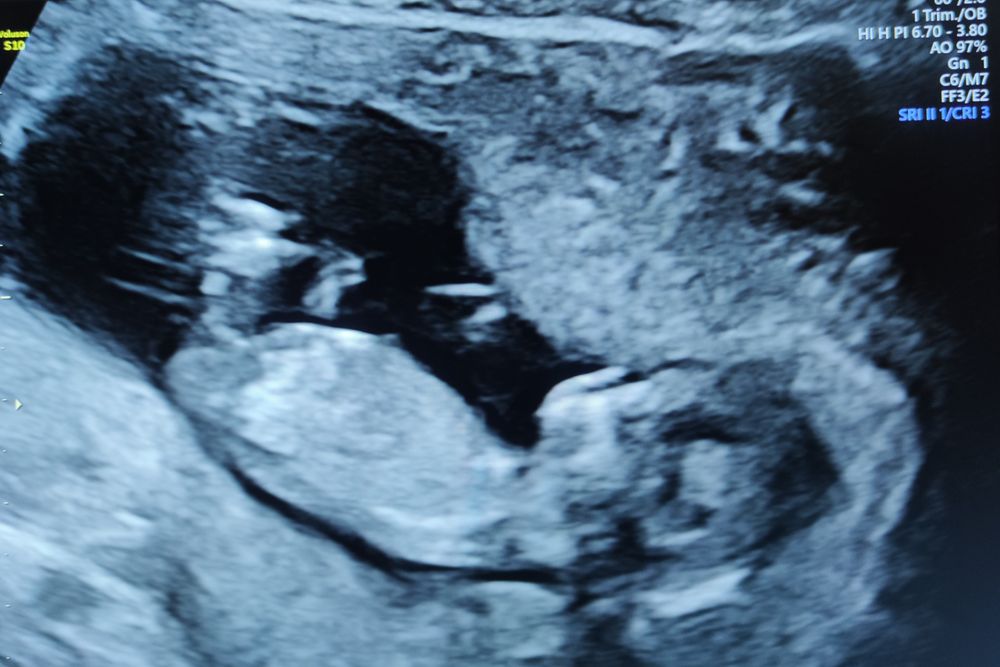

Всё о нашей беременностиНу что ж, самой не верится, но мы добрались до скрининга. Руки, ноги, нос - всё есть. Идем день в день. Даже переживать повода нет) Делала в ЖК. Очень все понравилось, отличная доброжелательная доктор, аппаратура вроде тоже неплохая, не знаю к чему придраться. И вот отсюда вопрос...